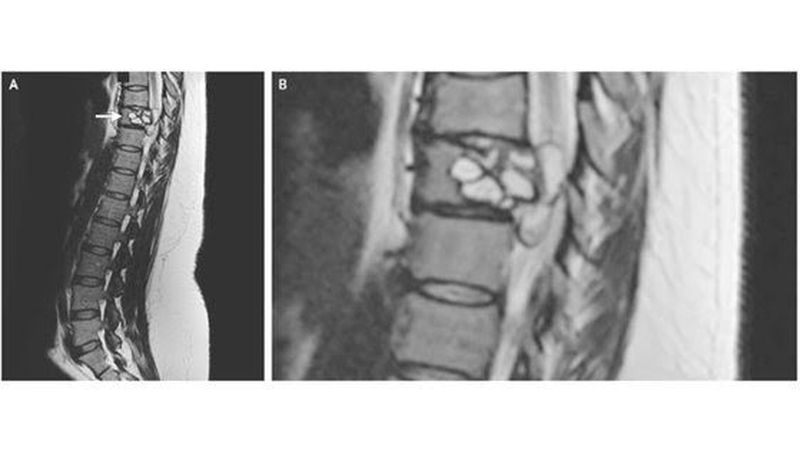

A woman who kept falling over and felt tingling in her legs was shocked to discover the cause.The 35-year-old ended up in hospital where medics scanned her spine. To their surprise, they found tapeworm larvae wriggling around the patient’s vertebrae. The French woman, who is not named, arrived at hospital complaining of suffering what felt like “electric shocks” running down her legs. She felt weak, and had experienced a number of falls. A scan showed a lesion at her 9th vertebra – in the middle of her spine. Surgeons investigated and found the lesion was in fact tapeworm larvae, caused by an infection of Echinococcus granulosus – a small tapeworm found in dogs and some farm animals.